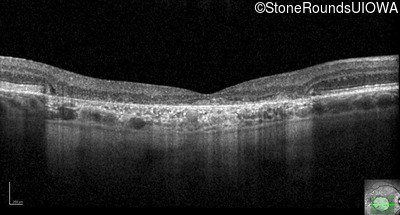

Optical Coherence Tomography - Left - 20/100 +2

Exemplar / OCT Stack